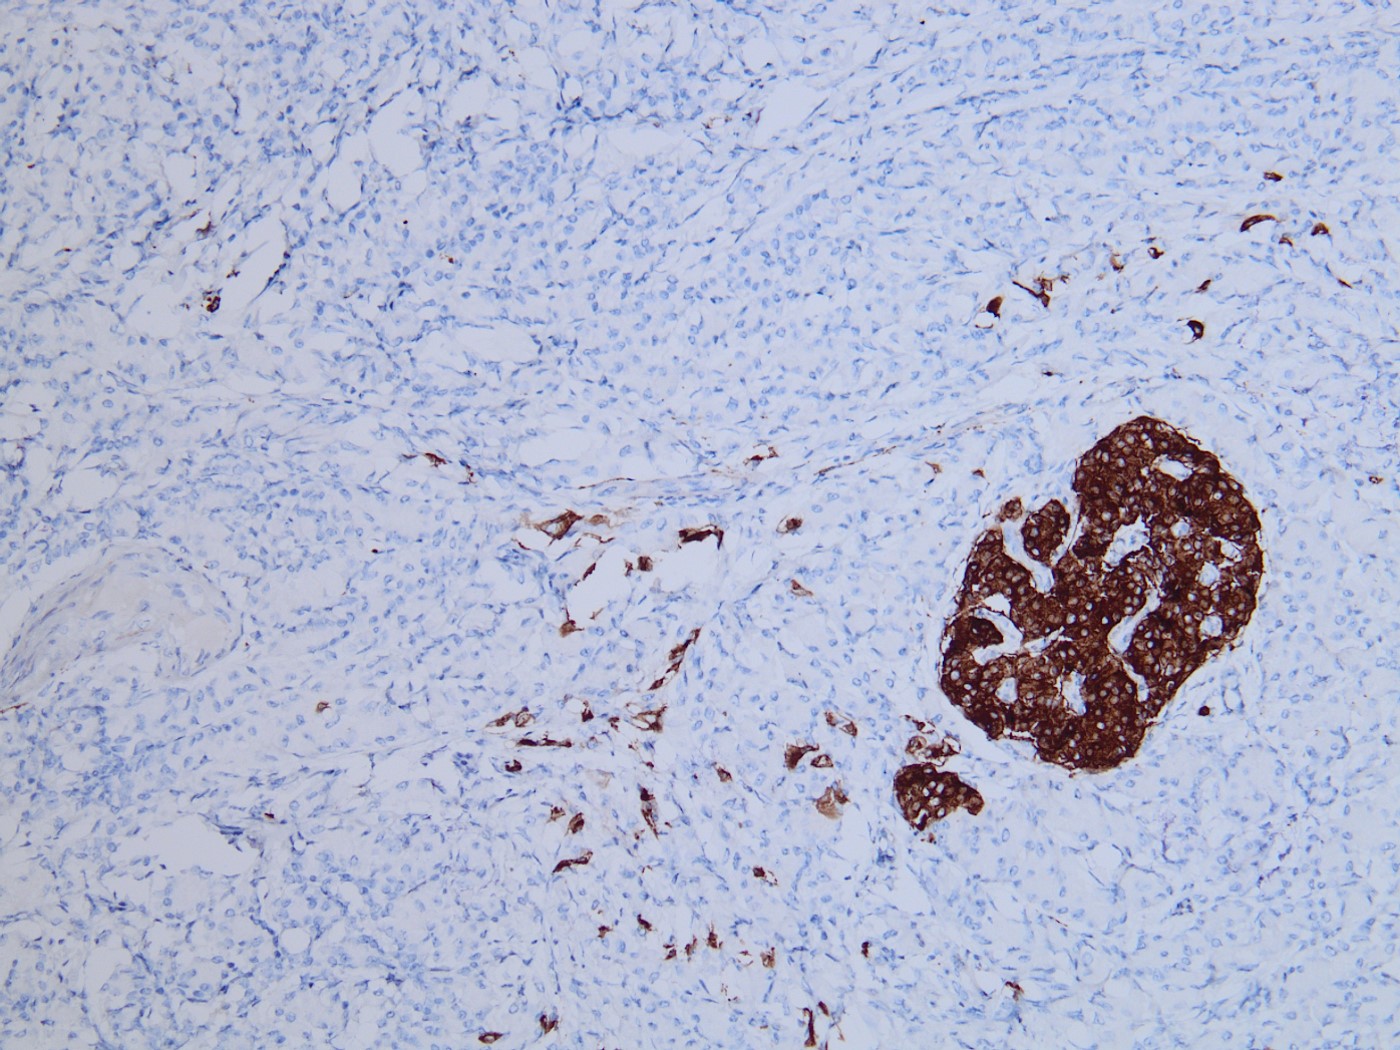

The tumor is solid and cellular with the individual cells displaying abundant granular cytoplasm and round monotonous nuclei with prominent nucleoli, configured in a vague acinar formation. These features are consistent with an acinar cell carcinoma, therefore positive staining for trypsin and BCL10 are expected (figures).

The main differential diagnosis in this case is a well differentiated neuroendocrine tumor. However, a stain for synaptophysin stain is negative, with an islet serving as an internal control. This finding rules out a neuroendocrine tumor, therefore chromogranin would also likely be negative. Acinar cell carcinoma can sometimes have weak staining for neuroendocrine markers, however the KI67 index should be high in acinar cell carcinoma. Pancreatoblastoma is also an important differential diagnosis for acinar cell carcinoma. The background of pancreatoblastoma is often that of an acinar pattern with corresponding trypsin positivity. However, pancreatoblastoma will contain squamoid nests that show nuclear staining for beta-catenin. Solid pseudopapillary neoplasm (SPN) should also be considered as a differential, as it is a solid and cellular neoplasm with bland cytology. However, acinar cell carcinoma lacks the distinctive small capillaries and pseudo papillae formation seen in SPN. SPN will also have characteristic nuclear beta catenin staining.